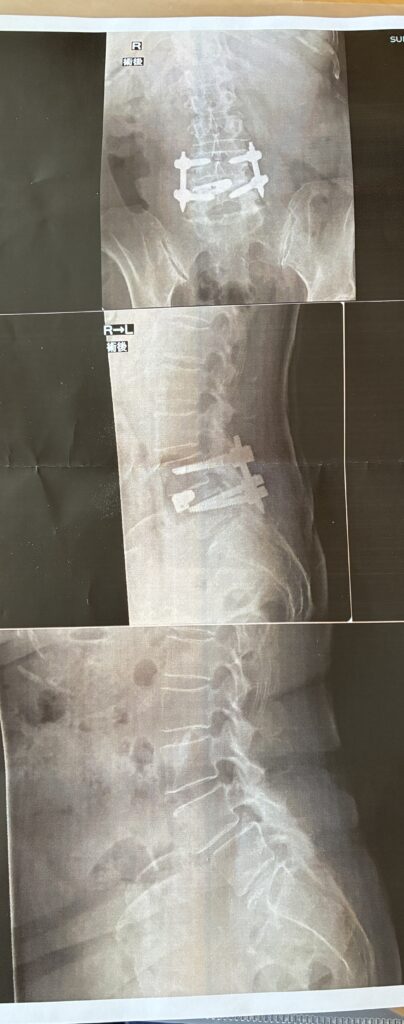

手術後のレントゲン写真を見せてもらう

その時、

手術後のレントゲン写真も見せてくれました。

ずれていた腰椎は

きちんと元の位置に戻され、

ボルトでしっかり固定されているのがはっきり分かる画像でした。

ずれていた腰椎が、ボルトで固定されているのが分かる

正直、

「ボルトで固定する手術」と聞いた時は

想像するだけで不安でした。

でも実際の画像を見て、

そして先生の

「成功しています」

という言葉を聞いて、

胸の奥にあった緊張が

すっとほどけたのを覚えています。